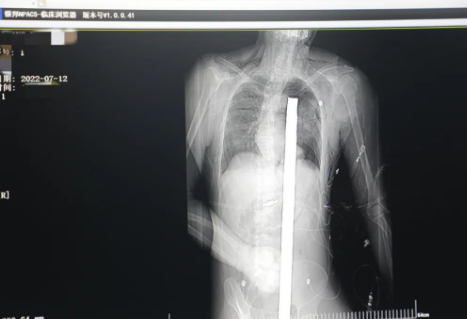

突發(fā)!太疼了,1.2米長的螺紋鋼從男子會(huì)陰部垂直穿入胸腔......7月12日下午16時(shí)10分,西安一處工地的一名26歲工友,不慎從10多米的高空墜落,不幸的是工地上一根直徑3厘米的螺紋鋼從男子會(huì)陰部垂直穿入體內(nèi),工地上的工友們小心翼翼地將連著的鋼筋截?cái)唷G闆r危急,立即送往西安國際醫(yī)學(xué)中心醫(yī)院急救中心,此時(shí)正是下午17時(shí)00分。

時(shí)間就是生命!此時(shí),西安國際醫(yī)學(xué)中心醫(yī)院展開了一場與生命賽跑的搶救,第一時(shí)間開辟綠色通道,急診X光片及CT顯示:異物經(jīng)會(huì)陰部貫穿盆腔、腹腔到達(dá)左側(cè)胸腔主動(dòng)脈弓水平。醫(yī)院創(chuàng)傷中心立即啟動(dòng)應(yīng)急預(yù)案,劉延彤副院長親臨指揮,下午17點(diǎn)48分,當(dāng)患者被送達(dá)手術(shù)室,胸外、心外、肝膽外科、胃腸外科,泌尿外科及麻醉科等多學(xué)科專家聯(lián)手對(duì)這名工友進(jìn)行“縱劈胸骨 前外側(cè)開胸探查 氣管及主支氣管修補(bǔ) 肺修補(bǔ) 血胸清除 開腹探查止血 腹膜后及盆腔探查......”手術(shù)。

情況緊急!術(shù)中探查后發(fā)現(xiàn),長120cm直徑3cm的螺紋鋼經(jīng)患者右側(cè)會(huì)陰部穿入,傷及直腸,途徑膀胱后方,左側(cè)髂總動(dòng)靜脈之間傷及左腎后,經(jīng)胰腺后方在肝脾之間穿破膈肌,在下肺靜脈前方穿入左肺穿破氣管及左右主支氣管膜部,止于主動(dòng)脈弓下水平,穿入體內(nèi)的部分達(dá)到75cm。